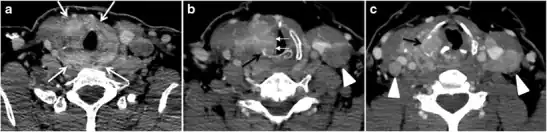

Fig. 6. A 61-year-old female patient with locally aggressive PTC. an Enhanced axial CT scan of the neck demonstrates a heterogeneous infiltrative thyroid mass. This mass diffusely involves the entire gland and circumferentially encases the trachea with involvement of bilateral tracheoesophageal grooves (white arrows). b, c Additional axial cranial images show right cricoid cartilage destruction (black arrows in b), right thyroid cartilage destruction (black arrow in c), right vocal cord paralysis (white arrows in b), and bilateral cervical lymphadenopathy (arrowheads).[1]

The radiologist must evaluate the central structures draping the thyroid gland including the trachea, oesophagus, larynx, and pharynx, as well as the recurrent laryngeal nerve. Invasion is suspected if the thyroid mass abuts the airway or oesophagus for more than 180 degrees. Luminal deformity, mucosal thickening and mucosal focal irregularity are more specific indicators of invasion. Obliteration of the fat planes of the tracheoesophageal groove in three axial images and signs of vocal cord paralysis are indicative of recurrent laryngeal nerve invasion. Invasion of these central structures meets the criteria for T4a disease (Figs. 5 and and6)6).[1]

Arterial invasion constitutes T4b disease, which may preclude curative surgery. More than 180 degrees of arterial encasement is suggestive of invasion, however, arterial deformity or narrowing is much more suspicious for invasion. The carotid artery is the most commonly involved artery; however, the mediastinal vessels should also be examined. Encasement of the carotid artery or mediastinal vessels for more than 270 degrees is unlikely to be resectable. On the other hand, occlusion or effacement of the internal jugular vein can occur without invasion and does not influence surgical resectability or staging. Asymmetry of the strap muscle and the tumour abutting its external surface are signs of an invasion. However, invasion of the pre-vertebral musculature is more challenging, as a large lesion can compress the muscle without invasion (Figs. 5 and and6)6).[1]